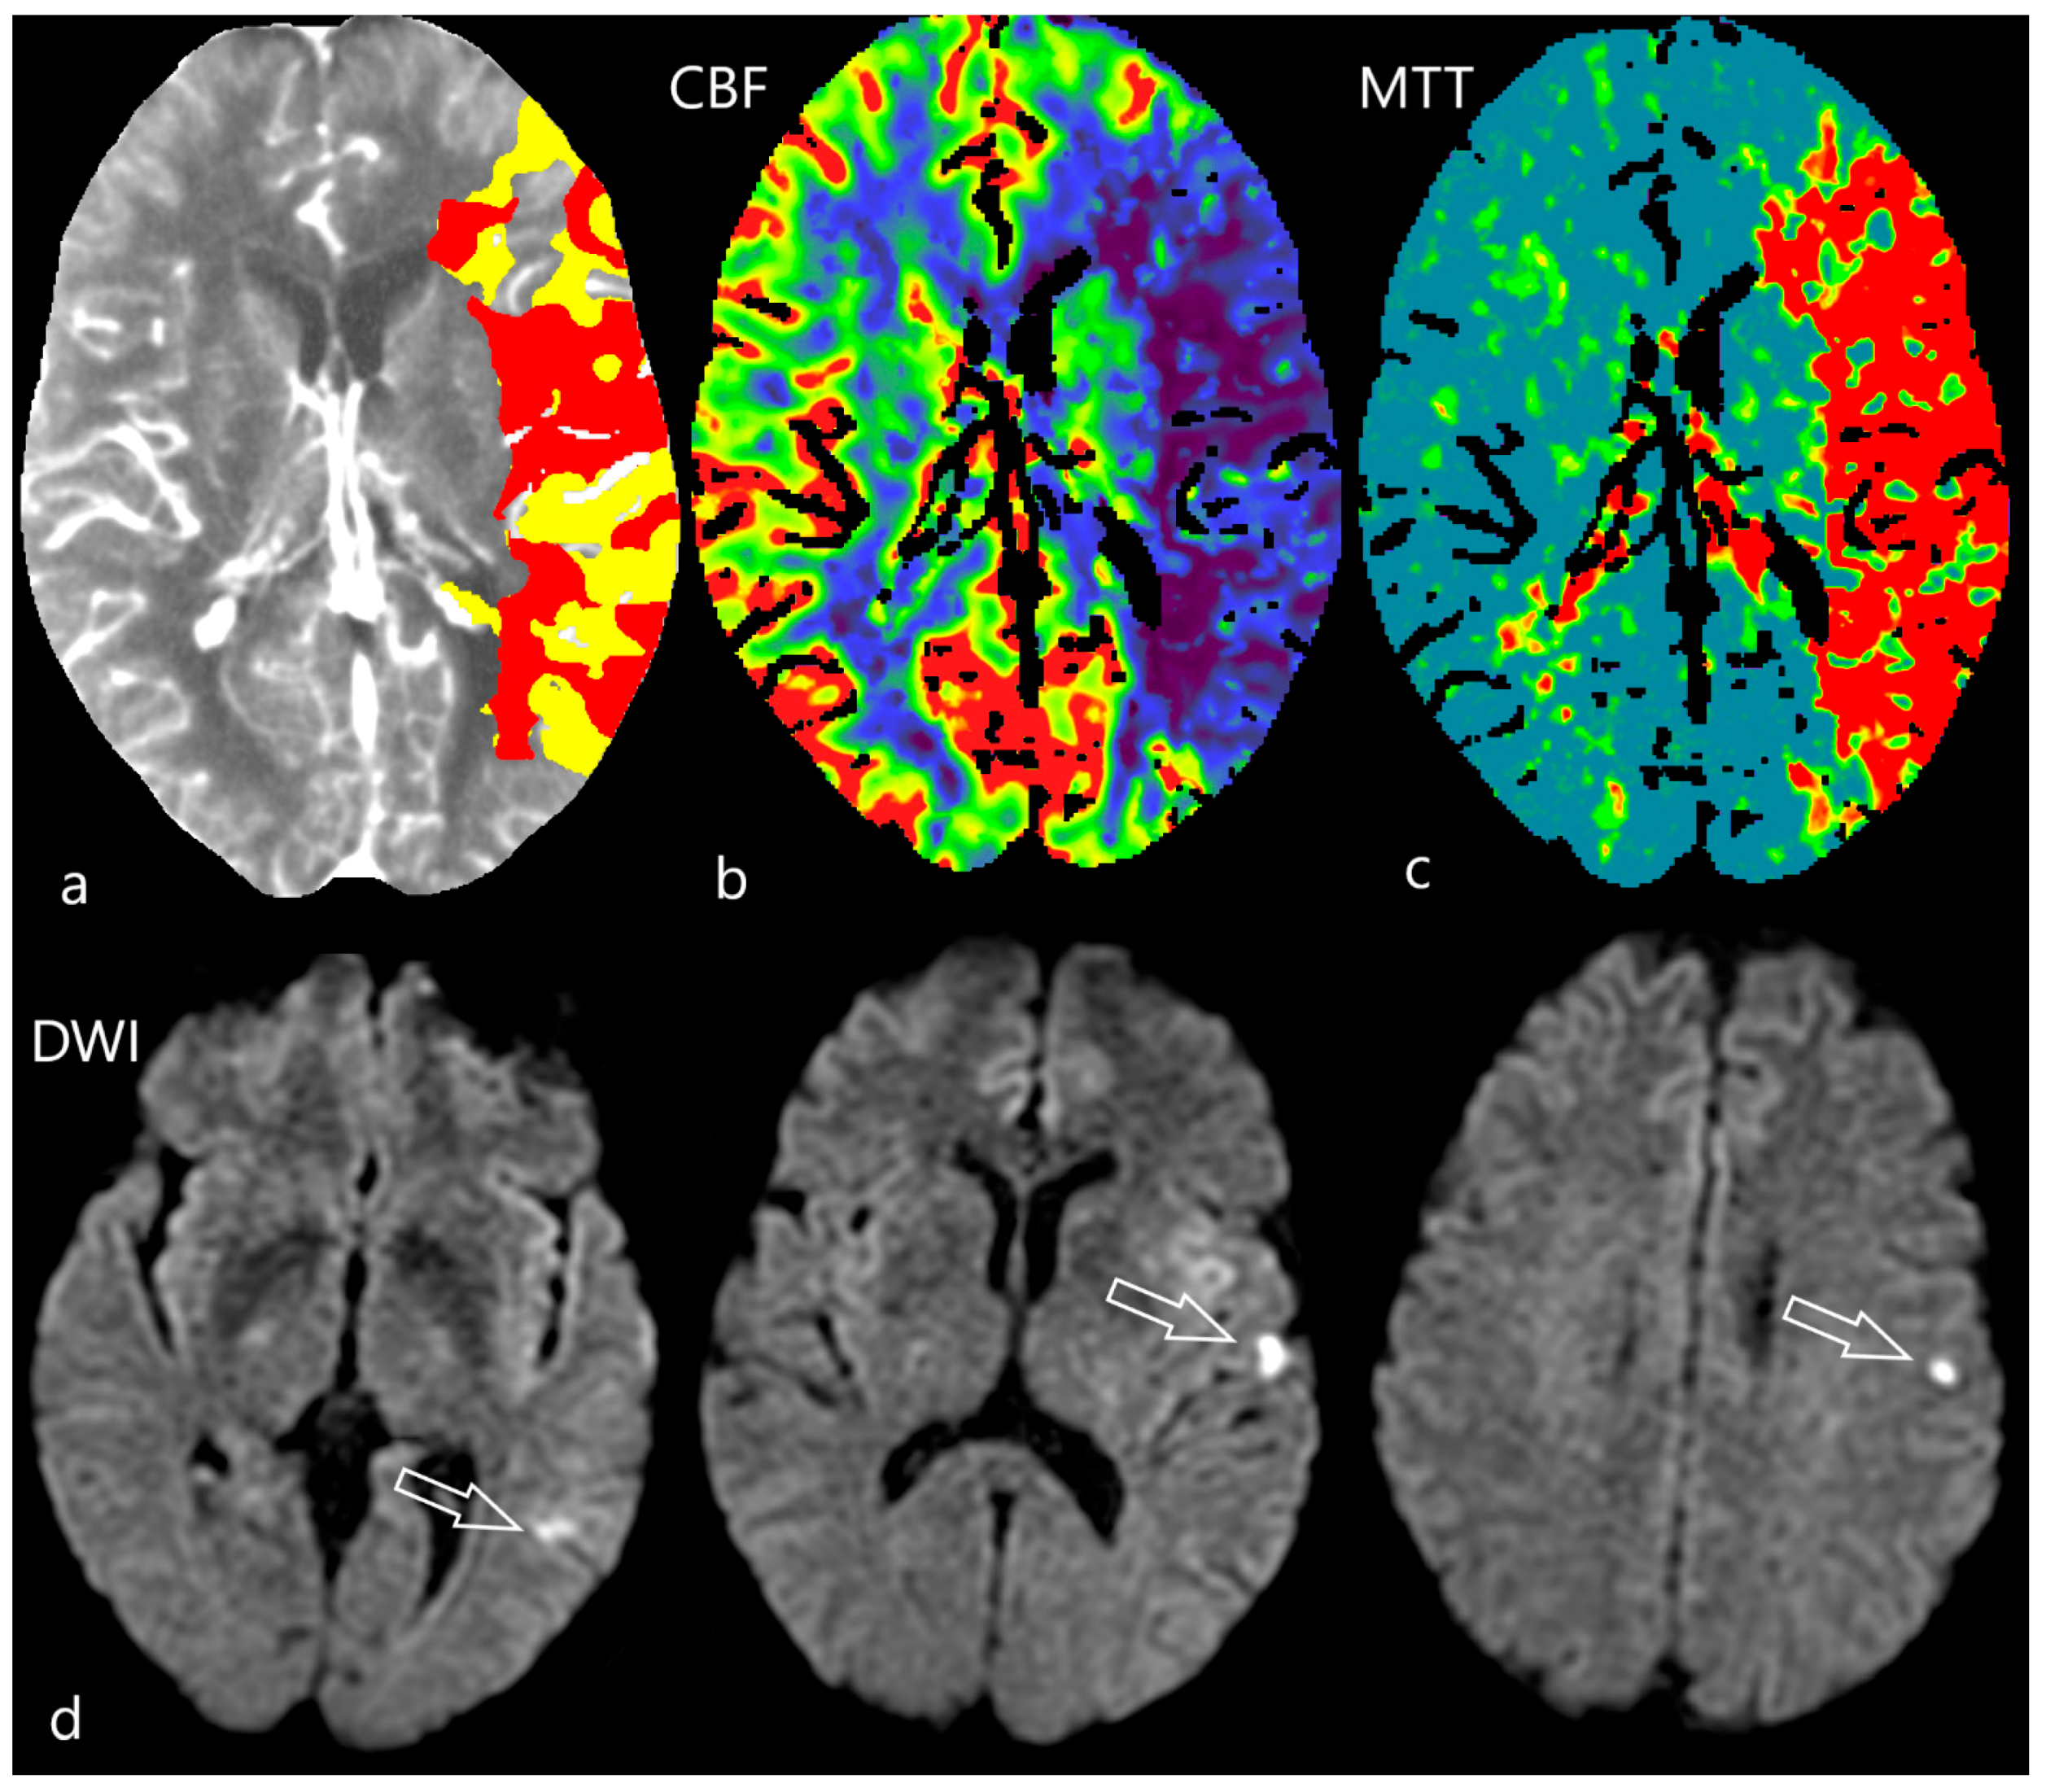

5. The Third Task: To Estimate the Ischemic Core

- Kremenova, K.; Holesta, M.; Peisker, T.; Girsa, D.; Weichet, J.; Lukavsky, J.; Malikova, H. Is limited-coverage CT perfusion helpful in treatment decision-making in patients with acute ischemic stroke? Quant. Imaging. Med. Surg. 2020, 10, 1908–1916. [Google Scholar] [CrossRef]

- Martins, N.; Aires, A.; Mendez, B.; Boned, S.; Rubiera, M.; Tomasello, A.; Coscojuela, P.; Hernandez, D.; Muchada, M.; Rodríguez-Luna, D.; et al. Ghost Infarct Core and Admission Computed Tomography Perfusion: Redefining the Role of Neuroimaging in Acute Ischemic Stroke. Interv. Neurol. 2018, 7, 513–521. [Google Scholar] [CrossRef]

- Boned, S.; Padroni, M.; Rubiera, M.; Tomasello, A.; Coscojuela, P.; Romero, N.; Muchada, M.; Rodríguez-Luna, D.; Flores, A.; Rodríguez, N.; et al. Admission CT perfusion may overestimate initial infarct core: The ghost infarct core concept. J. Neurointerv. Surg. 2017, 9, 66–69. [Google Scholar] [CrossRef]